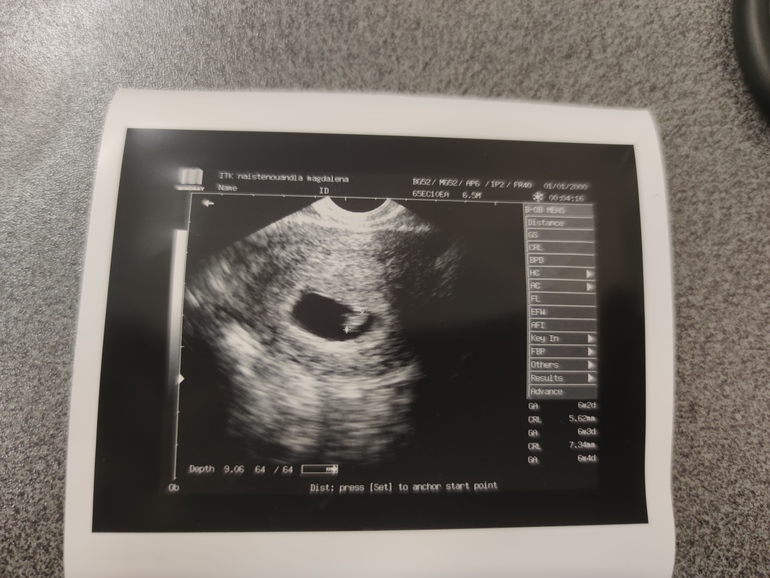

Счас дам 3 фото, узи во всех случаях вагинальное, срок по М 7-8 недель :)

Кто сейчас?

извините, может и мне подскажите, это у подружки)

Оо, вот тут сложно определить, по мне так прикрепление ровно по центру сверху. Вообще не вижу смещение ни в лево ни в право. Малыш- загадка))